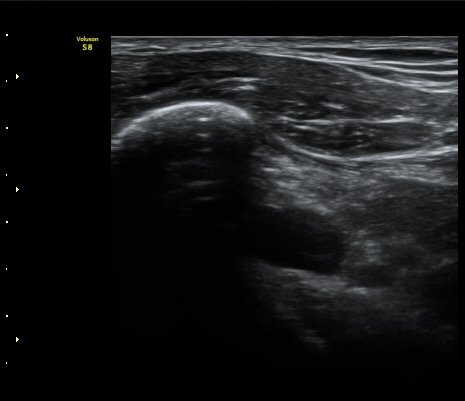

¿À±¸µ¹±â Á¾´Ü¸é°Ë»ç½Ã ¿À±¸ µ¹±â ³»Ãø, ¿À±¸µ¹±â ¾Æ·¡¿¡ ¼ö¾×Àú·ù°¡ °üÂûµÈ´Ù(±×¸² 5, 6).